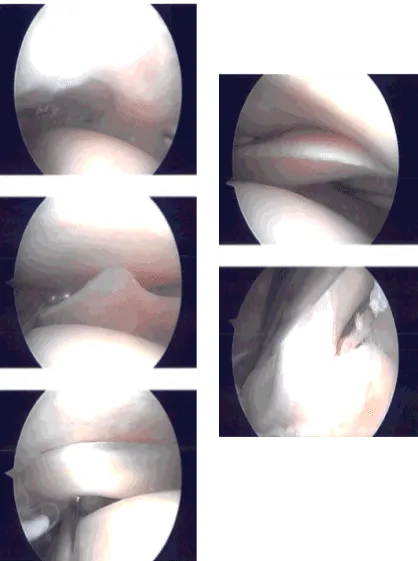

Entry portal was made laterally with a lateral parapatellar incision. Arthroscope was entered. Patellofemoral joint showed no injury. A medial plica could be seen. The scope was entered in the medial tibiofemoral compartment. Medial entry portal was made with the use of a spinal needle.

The medial compartment showed no tear of the medial meniscus. There was no cartilage tear. The scope was entered into an intercondylar notch. The ACL was intact with subtle degeneration.

The scope was entered into the lateral compartment where there was some fraying of the medial margin of lateral meniscus which was cleaned with the use of shaver and biter. No other meniscal tear was found.

Scope was entered into the patellofemoral compartment where there was no cartilage damage though there was patellar maltracking. There was a medial synovial plica which was prominent. It was debrided with the use of a shaver.

Final pictures were taken and saved. The knee was irrigated and drained. Knee was closed with nylon # 3-0. Naropin 9 cc mixed with 40 mg of Depo-Medrol was injected into the knee.

Intraoperative Arthroscopy Images